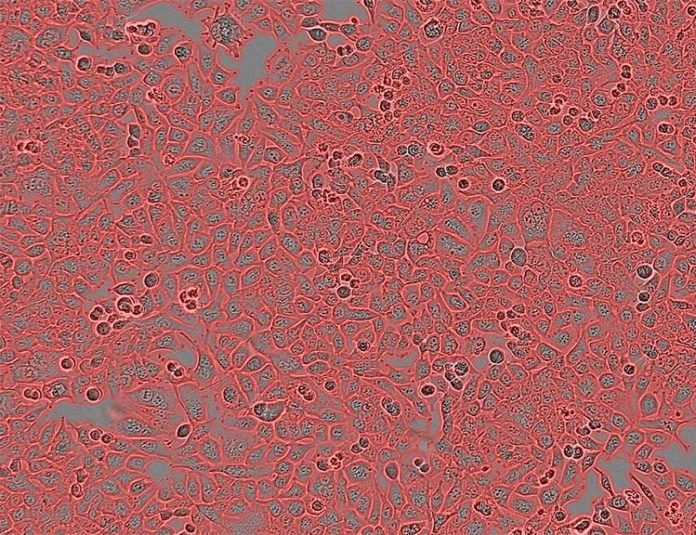

El estudio se realizó en células cancerosas en cultivo y no en tumores reales

En el estudio, los investigadores utilizaron métodos bioinformáticos avanzados para cuantificar la aneuploidía en aproximadamente 1.000 cultivos de células cancerosas. Luego, compararon la dependencia genética y la sensibilidad a los fármacos de las células con un nivel alto de aneuploidía con las de las células con un nivel bajo de aneuploidía. Descubrieron que las células cancerosas aneuploides demuestran una mayor sensibilidad a la inhibición del punto de control mitótico, un punto de control celular que asegura la separación adecuada de los cromosomas durante la división celular.

«Debe enfatizarse que el estudio se realizó en células en cultivo y no en tumores reales, y para traducirlo al tratamiento de pacientes con cáncer, se deben realizar muchos más estudios de seguimiento. Sin embargo, si todo esto también resulta cierto en pacientes, nuestros hallazgos tendrían una serie de importantes implicaciones médicas«, concluye el Dr. Ben-David.